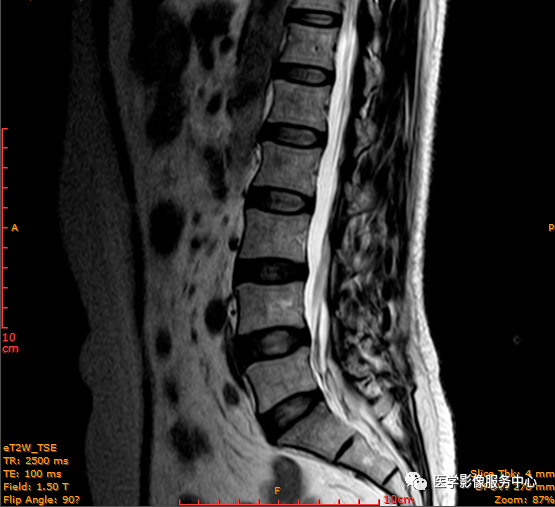

患者 女性 54岁 因腰背部疼痛不适数月,下腰时疼痛明显而入院;

病史:患者3个月前开始出现左侧腰背部酸痛不适,当时未重视,后腰背部疼痛加重,偶伴左下肢麻木伴小腿放射性疼痛,经休息有所好转,久坐后症状明显加重;

查体:L3-4、L4-5棘突处压痛(+),四肢肌力、肌张力正常,触痛觉正常,双侧膝腱反射正常,双侧跟腱反射正常,双侧巴彬斯基(-)。

临床诊断 :腰突症?故行腰椎MRI检查,图像如下:

矢状位PD压脂序列

这个患者腰椎间盘膨出程度不明显,神经根没有明显的受压,椎管未见明显狭窄,那这个患者腰疼的“罪魁祸首”是腰椎间盘膨出嘛?

大家有没有留意到还有哪个地方不正常呢?

L3-4椎间盘后缘可见点状高信号区(红色箭头所指处)

红色箭头所指的异常信号区是是什么呢?平时工作中大家有没有遇到这种情况,你会不会忽略这个异常信号?有没有想过这个椎间盘后缘高信号区是引起患者腰疼的重要因素呢?下面为大家重点介绍。